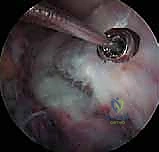

3. التصوير بالرنين المغناطيسي (MRI)

يُعد الدكتور هطيف من أشد المؤيدين لاستخدام الرنين المغناطيسي في هذه الحالات. لماذا؟ لأن الأشعة السينية تظهر العظام فقط، بينما الرنين المغناطيسي يظهر الأنسجة الرخوة.

* يساعد الرنين في التأكد من عدم وجود تمزق في الرباط الصليبي نفسه.

* يكشف عن أي إصابات مصاحبة، مثل تمزق الغضروف الهلالي (Meniscus Tear)، والذي يحدث في حوالي 30% إلى 40% من حالات كسر شوكة الظنبوب.

* يحدد بدقة ما إذا كان هناك أنسجة رخوة (مثل الغضروف الهلالي الأمامي) قد انحشرت تحت القطعة العظمية المكسورة، مما يمنع عودتها لمكانها الطبيعي، وهو ما يحتم التدخل الجراحي.